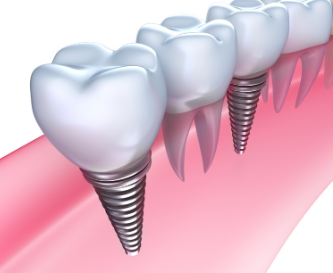

етИіОЭЪЧжжжВбРЕФЛљБОЙ§ГЬРВЃЌжжбРЭъГЩКѓВЂВЛЪЧвЛРЭгРвнЕФЃЌашвЊКУКУАЎЛЄжжжВбРЃЌзіКУШеГЃПкЧЛБЃНЁЃЌвдМАЖЈЦкЕНПкЧЛЛњЙЙНјааИДВщЁЃ

ВЂЗЧЫљгажжбРЖМашвЊетУДГЄЪБМфЃЌЯёЪЧЪ§зжЛЏЮобРђЂМДПЬжжжВОЭФмзіЕНАЮбРЁЂжжбРЁЂДїЙквЛВНЕНЮЛЁЃжСгкВЩгУФФжжжжбРЗНЪНЃЌНЈвщИїЮЛЛМепЬ§вНЩњЕФНЈвщЁЃ

ЁОЮТмАЬсЪОЁПжжжВбРЫфШЛЪЙгУЪБМфПЩвдГЄДяМИЪЎФъЃЌЕЋгыЮвУЧШеГЃЕФЛЄРэКЭБЃЛЄЪЧЗжВЛПЊЕФЁЃвђДЫЃЌЮвУЧИќгІИУефЯЇЕкЖўДЮгЕгаЕФбРГнЕФЛњЛсЃЌИќгІИУАЎЛЄЫќЁЃБОдТРШЗЛЪЅНрПкЧЛвНдКПкИЃМЦЛЎНјаажаЃЌжжКУАыПкбРНіаш18000дЊЃЌЬиМлжжжВЬх2980дЊЃЌСэЭтЛЙгаПкЧЛМьВщШЏКЭЯжН№ЕжгУШЏЕШФњРДФУЁЃФњПЩЕуЛїдкЯпзЩбЏЛђЪЧВІДђРШЗЛЪЅНрПкЧЛвНдКЕФАЎбРШШЯпЃК0316—2285777ЃЌНјаадЄдМЃЌЮвУЧЕФдкЯпвНЩњЛсЯъЯИЮЊФњНтД№ЁЃ